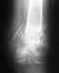

Основная часть смещенных фрагментов суставной площадки большеберцовой кости не вправлена и не была фиксирована. Все уже срослось в неправильном положении. Восстановить форму суставной поверхности и трудно, и, главное, это не обеспечит здоровый сустав. Вариант с артродезом тут вполне уместен. Способность нормально ходить как раз артродез и обеспечит.